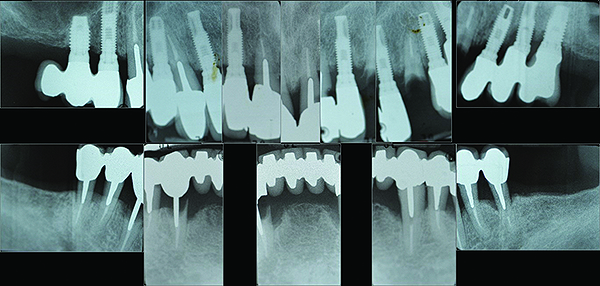

Fig 16. Post-treatment full-mouth radiographs.

Figure 16

The maxillary prototype was adjusted, polished, and left to function with the mandibular provisional. The definitive maxillary zirconia restoration was then completed from the information provided by the prototype, and the cutbacks for the facial porcelain (Nos. 6 through 11) were done after milling but before sintering. Subsequently, the mandibular prototype was adjusted to the sintered and colored maxillary zirconia framework before the application of porcelain to Nos. 6 through 11 and final glazing (Figure 11). Following this step, the mandibular definitive monolithic zirconia restoration was milled, colored, and sintered. The facial porcelain (Nos. 6 through 11) was applied, and then both maxillary and mandibular restorations were stained and glazed (Figure 12). Both bridges were inserted at the same time (Figure 13 through Figure 15). Minor occlusal adjustments and oral hygiene access was verified and the zirconia surfaces polished. The bridge screws were torqued to 20 Ncm according to the manufacturer’s recommendation, and No. 24 was luted with a provisional cement. Postoperative radiographs were taken (Figure 16).

After initial consultation, the preoperative full-mouth radiographs were obtained from the referring periodontist (Figure 1). To address the immediate concern of the patient, replacement of the original crown on tooth No. 11 was provisionally secured to the supporting root. Diagnostic study casts were made of the existing clinical conditions (Figure 2). A complete dental and medical assessment and identification and explanation of treatment objectives was performed. The patient was referred back to the periodontist for confirmation of the implant and periodontal treatment proposals. This included a cone-beam computed tomography (CBCT) scan of the mandible (Figure 3) to aid in optimal implant placement.8 This was then coordinated with the development of the prosthetic sequencing and design. After presentation of the completed treatment plan to the patient, informed consent was obtained.